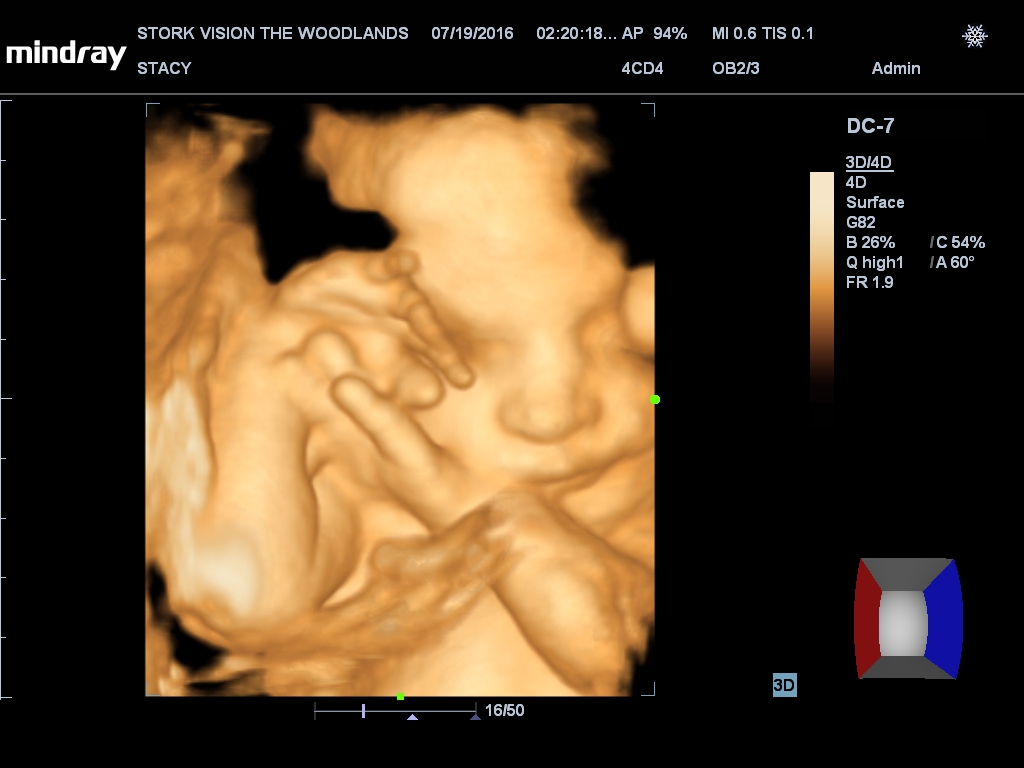

Best moment the week: Seeing Juliette on the 3D/4D ultrasound. So amazing!